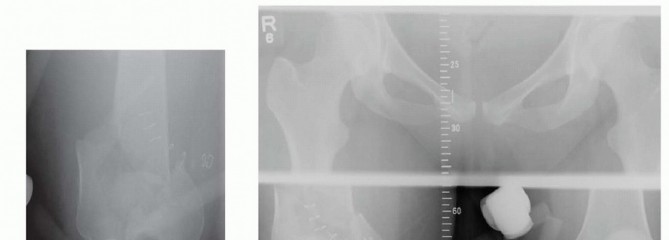

* FIG 2 • Mechanical and anatomic axes of the lower extremity; the 9 degrees of valgus at the knee is noted. The neurovascular structures about the knee are at risk when an injury of the distal femur occurs. At the canal of Hunter, roughly 10 cm proximal to the knee on the medial side, the superficial femoral artery enters the popliteal fossa (see FIG 3C). Posterior to the knee, both the popliteal artery and the tibial nerve are at risk at the fracture site ( FIG 3D). ## PATHOGENESIS As mentioned, there is a bimodal distribution in terms of age in the epidemiology of distal femur fractures. This relates to the mechanism of injury. High-energy and low-energy injuries occur. High-energy injuries usually are from motor vehicle accidents and occur in the young patient. There is a direct impact onto the flexed knee, such as from the dashboard. These patients often have associated injuries such as a hip fracture or dislocation or vascular or nerve injury. These high-energy injuries generally result in comminuted fractures, mostly of the metaphyseal region. The comminution can be articular as well. Low-energy injuries usually occur in the elderly patient who falls from a standing height. The axial loading is accompanied by either varus or valgus with or without rotation. The osteoporotic bone in these individuals leads to fracture. The fracture pattern can vary from the most simple extra-articular type to the most complex intraarticular injury. Owing to the gastrocnemius complex, an apex posterior deformity of the condyles occurs as the fragments are flexed because of the muscle attachment. ## NATURAL HISTORY Fractures of the distal femur that have intra-articular displacement can lead to severe posttraumatic arthritis if left untreated. Operative treatment has led to a 32% decrease in poor outcomes. 19 ## PATIENT HISTORY AND PHYSICAL FINDINGS Direct physical examination of the knee with a distal femur fracture is limited primarily because of pain and the obvious nature of the injury. The patient presents with a swollen and tender knee after either a fall or some high-energy trauma (motor vehicle or motorcycle accident). A large hemarthrosis is present. Any attempts at range of motion result in severe pain, and significant crepitus is usually noted with palpation. If there is concern for an open knee joint, the joint can be injected after a sterile preparation to see whether the knee joint communicates with any wound. The physical examination is directed primarily at ascertaining the neurovascular status of the lower limb and determining whether any associated injuries exist, especially the hip (see Exam Table for Pelvis and Lower Extremity Trauma, pages 1 and 2). If there are any small wounds or tenting of the skin anteriorly, the fracture should be considered as being open. It is important to check for pulses. If diminished or absent, pulses should be assessed with Doppler. The ankle-brachial indices should be obtained if there is a concern for arterial injury. Any side-to-side difference or value less than 0.9 warrants an arteriogram. Computed tomography (CT) arteriogram has been used with increasing frequency as well in cases where there is concern ( FIG 4). Nerve function should be checked. Sensation and both active dorsiflexion and plantarflexion must be assessed. ## IMAGING AND OTHER DIAGNOSTIC STUDIES The initial imaging study is always plain radiographs. Anteroposterior (AP) and lateral radiographs of the knee should be obtained initially. Traction films should be obtained if there is severe comminution of either the metaphysis or articular surface. This aids in the preoperative planning. 467

### FIG 4 • A,B. Coronal and sagittal CT angiography images showing intact femoral artery in a severely comminuted distal femur fracture (red arrows). Dedicated knee films should always be obtained in the assessment of distal femur fractures. Additionally, the entire femur, to include the hip and knee, should be imaged to look for possible extension and associated injuries and to allow for preoperative planning ( FIG 5). In cases of severe comminution, radiographs of the contralateral knee can aid in preoperative planning as well. A dedicated CT scan is an important adjunct to the preoperative planning when there is articular involvement ( FIG 6). Generally, extra-articular distal femur fractures do not require a CT scan. However, it has been shown that coronal fractures may be missed on plain films, and thus there is a low threshold for obtaining a CT scan for fractures of the distal femur. 11 If the fracture pattern warrants a temporary bridging external fixator, it is best to obtain the CT scan after placement of such a fixator for better definition. Coronal and sagittal reconstructions should be requested. Three-dimensional images can be created from most CT scans. This can also aid in the preoperative planning ( FIG 7A,B). Subtle sagittal plane rotational malalignment between condyles can be assessed ( FIG 7C). If associated soft tissue injury is suspected, such as ligamentous tears or tendon ruptures, then magnetic resonance imaging (MRI) may be indicated. Routine use of MRI, however, is not needed. ## DIFFERENTIAL DIAGNOSIS Proximal tibia fracture Femoral shaft fracture Septic knee Patella fracture Anterior cruciate ligament rupture Knee dislocation ## NONOPERATIVE MANAGEMENT There are few relative indications for nonoperative management of distal femur fractures: Poor overall medical condition Patient has severe comorbidities and is too sick for surgery. Patient has extremely poor bone stock. Spinal cord injury (paraplegia or quadriplegia) Some special situations may warrant nonoperative care on case-by-case basis. Nondisplaced or minimally displaced fracture Select gunshot wounds with incomplete fractures Extra-articular and stable Unreconstructable Lack of experience by the available surgeon or lack of equipment or appropriate facility to adequately treat the injury. Transfer is indicated in these situations; otherwise, nonoperative treatment may be the only option. There are several methods for nonoperative treatment. Skeletal traction Cast bracing Knee immobilizer Long-leg cast There are acceptable limits for nonoperative management: Seven degrees of varus or valgus Ten degrees of anterior or posterior angulation. A flexion deformity is less well tolerated than an extension deformity. Up to 1 to 1.5 cm of shortening Two to 3 mm of step-off at the joint surface 469